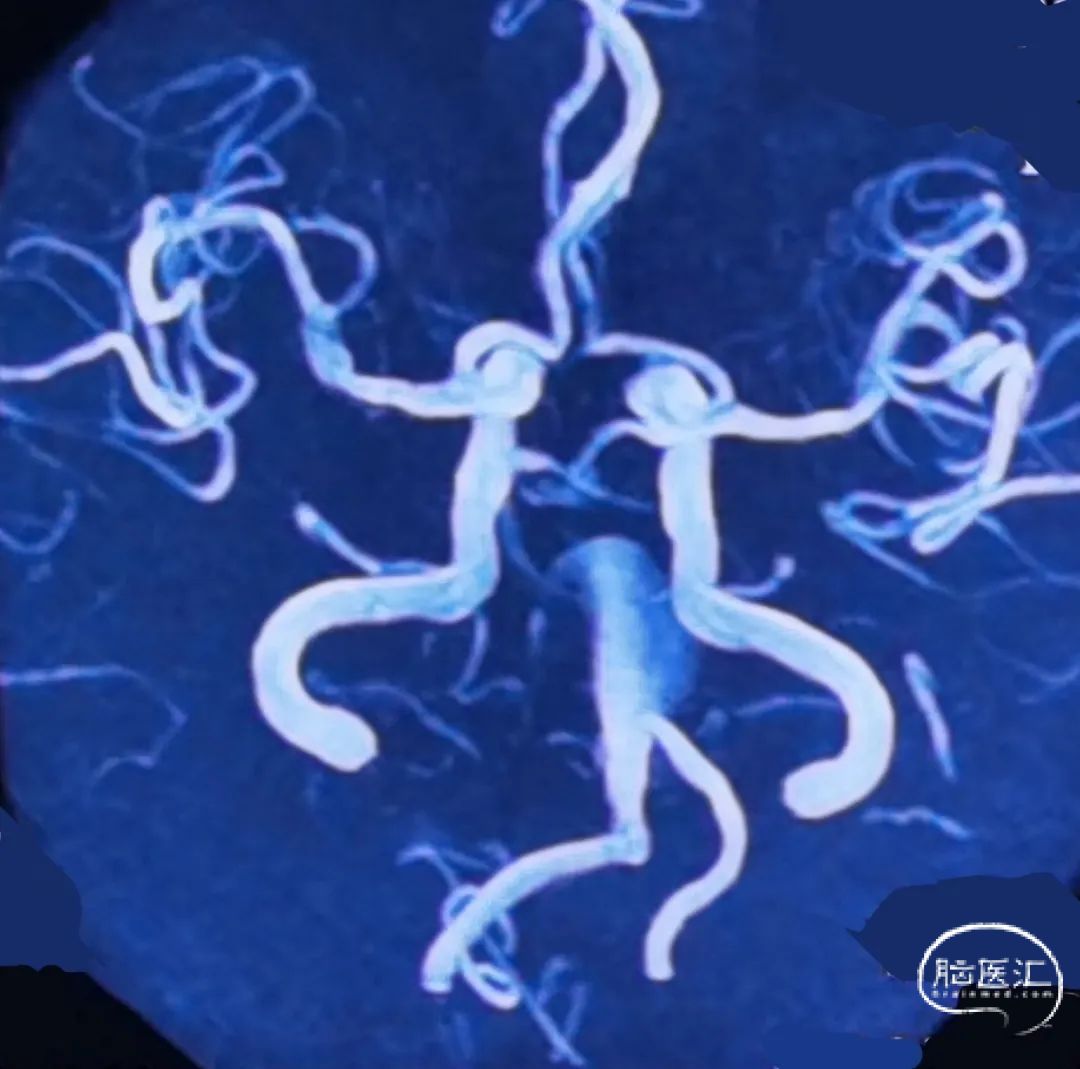

右侧椎动脉

左侧椎动脉

1、该患者属于串联动脉瘤,累及左椎动脉V4段末端和基底动脉近端。其中基底动脉近端为富穿支区域,常规介入治疗面临较高的缺血并发症。

3、患者双侧椎动脉均势发育,一期栓塞左椎动脉瘤及左椎动脉,不会导致严重后循环缺血症状,同时有助于血流导向装置的导流作用,促进基底动脉瘤的愈合。但栓塞椎动脉时,要关注附近的重要血管分支,比如脊髓后动脉。